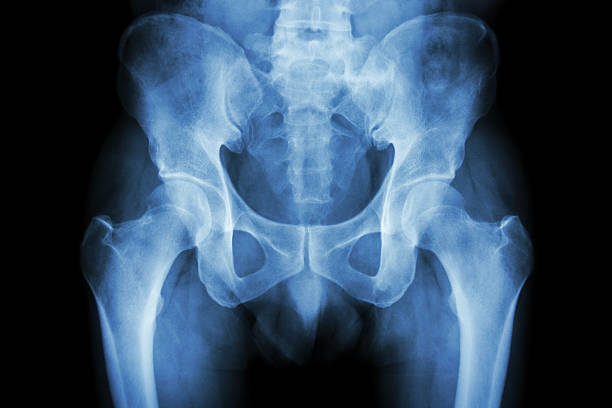

고관절은 걷기, 앉기, 서기 등 일상생활의 모든 움직임에 중요한 역할을 하는 부위입니다. 하지만 이 부위에 통증이 생기면 움직임이 크게 제한되고 삶의 질이 떨어질 수 있죠. 오늘은 많은 분들이 궁금해하는 고관절 통증 증상 10가지와 치료 정리에 대해 자세히 알아

고관절 통증은 단순한 근육통에서부터 관절염, 골절, 신경계 문제까지 다양한 원인으로 발생할 수 있습니다. 증상과 원인을 정확히 파악하는 것이 빠른 치료와 예방의 첫걸음입니다. 특히 고관절 통증 증상 10가지와 치료 정리를 통해 본인 상태를 체크해보는 것이 중요합니다.